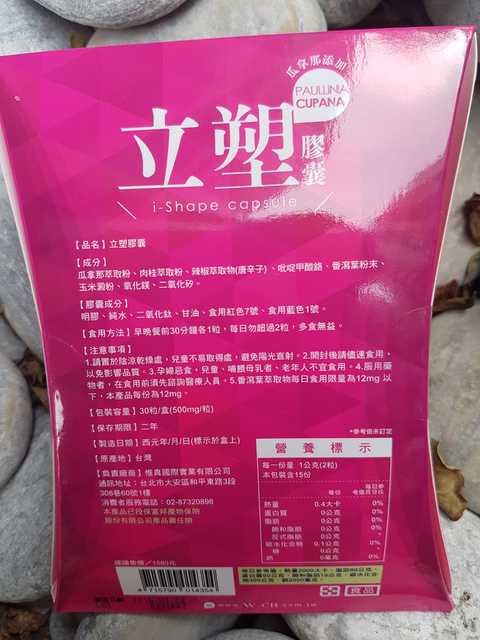

Supercut塑魔纖立塑膠囊的成分有:瓜拿那萃取粉、肉桂萃取粉、辣椒萃取物(唐辛子)、吡啶甲酸鉻、番瀉葉粉末、玉米澱粉、氧化鎂、二氧化矽。

之前上過相關課程,成分表是依照每項成分的多寡來排列順序,排在最前面的就是產品的主要成分!

食用方式:早晚餐前30分鐘各1粒,每日不超過2粒。(多食無益)

番瀉葉萃取物每日食用限量為12mg以下,

番瀉葉萃取物每日食用限量為12mg以下,